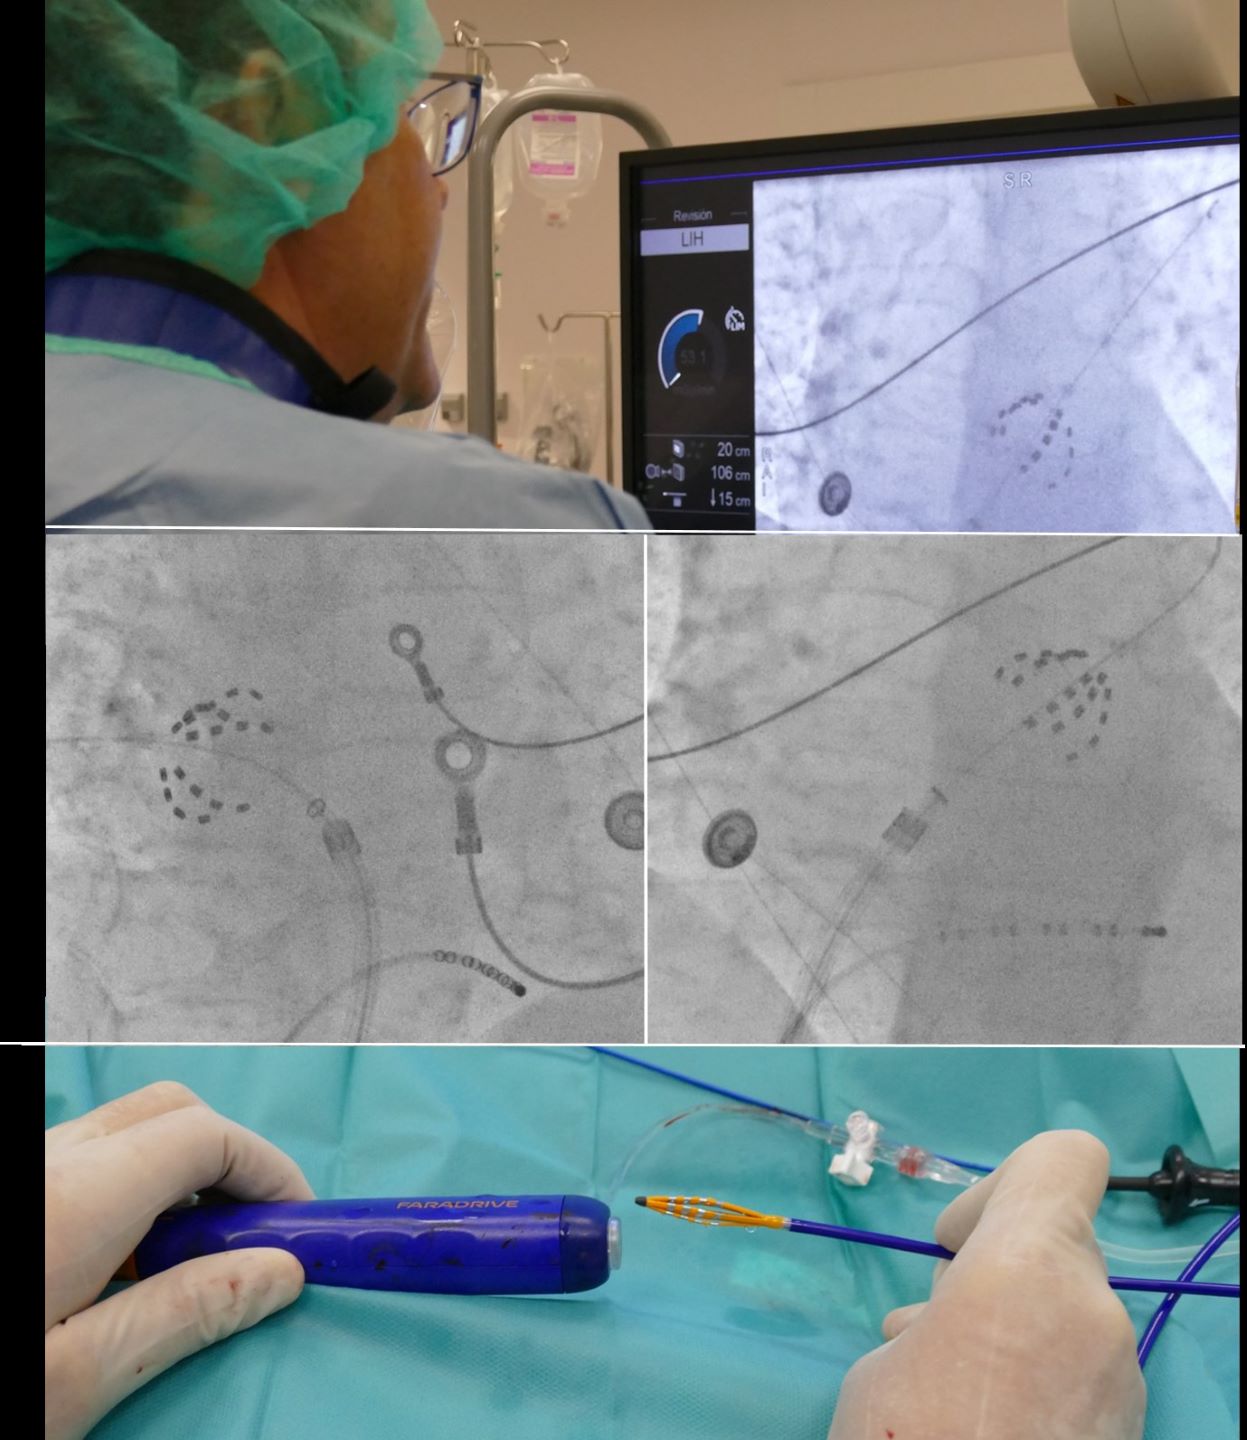

Para evitar estos efectos indeseados recientemente se ha incorporado en todo el mundo la ablación por electroporación, que consiste en la emisión, a través de un catéter, de campos eléctricos que destruyen selectivamente las células cardiacas que propagan la fibrilación auricular, respetando el resto de tejidos. "El efecto observado de la electroporación en la actividad eléctrica cardiaca es inmediato, lo que permite realizar la intervención en menos tiempo y de una forma, incluso, más segura", destaca el Dr. Fontenla.